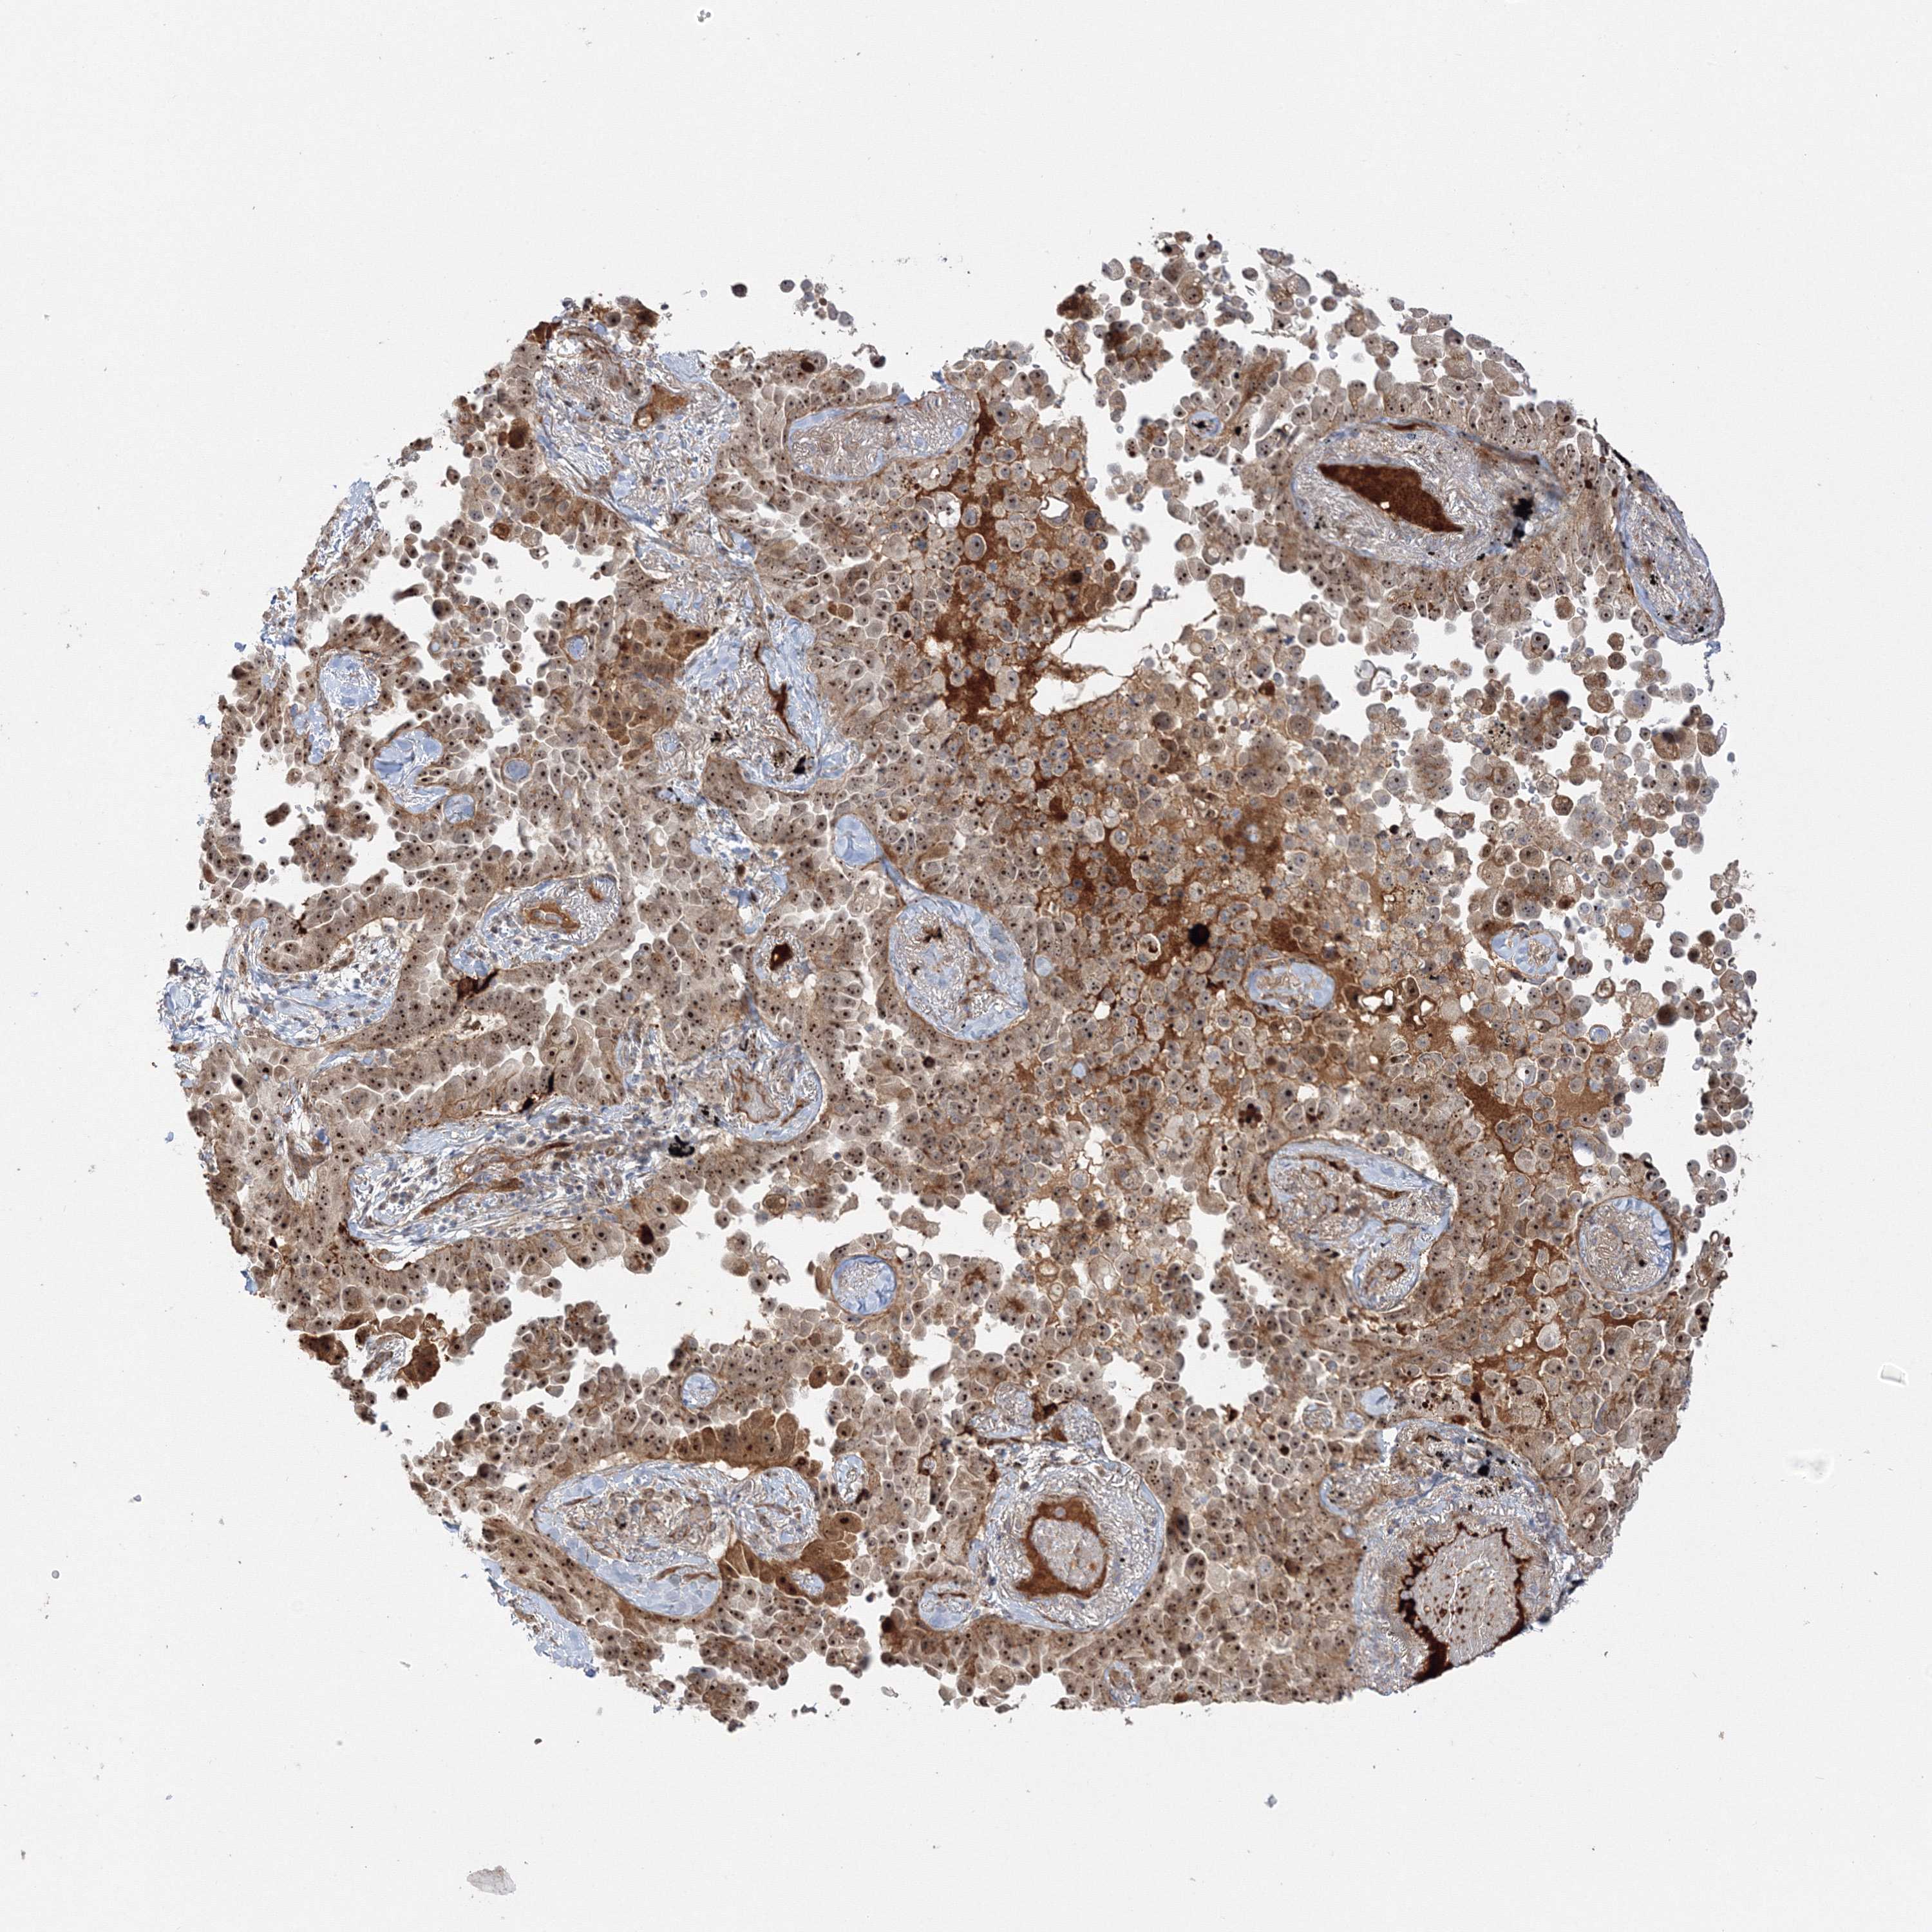

LUNG ADENOCARCINOMA (VALIDATION) - Interactive survival scatter ploti

The Survival Scatter plot shows the clinical status (i.e. dead or alive) for all individuals in the patient cohort, based on the same data that underlies the corresponding Kaplan-Meier plots. Patients that are alive at last time for follow-up are shown in blue and patients who have died during the study are shown in red.

The x-axis shows the expression levels (FPKM) of the investigated gene in the tumor tissue at the time of diagnosis. The y-axis shows the follow-up time after diagnosis (years). Both axes are complimented with kernel density curves demonstrating the data density over the axes. The top density plot shows the expression levels (FPKM) distribution among dead (red) and alive patients (blue). The right density plot shows the data density of the survived years of dead patients with high and low expression levels respectively, stratified using the cutoff indicated by the vertical dashed line through the Survival Scatter plot. This cutoff is automatically defined based on the FPKM cutoff that minimizes the p-score. The cutoff can be changed by dragging the vertical line or by entering a cutoff value in the square labeled "Current cut-off".

Under the Survival Scatter plot the p-score landscape (black curve; left axis) is shown together with dead median separation (red curve; right axis). Dead median separation is the difference in median mRNA expression between patients who have died with high and low expression, respectively. It is calculated as follows: median FPKM expression of dead patients with high expression - median FPKM expression of dead patients with low expression. This is intended to aid the user in visually exploring custom cutoffs and the associated p-scores and dead median separation.

Individual patient data is displayed and can be filtered by clicking on one or more of the category buttons on the top of the page. Categories describing expression level and patient information include: high, low, alive, dead, female, male and tumor stages. The scale of the x-axis can be toggled between linear and log-scale by clicking on the "x log" button. Mouse-over function shows TCGA ID, patient information and mRNA expression (FPKM) for each patient.

& Survival analysisi

Kaplan-Meier plots summarize results from analysis of correlation between mRNA expression level and patient survival. Patients were divided based on level of expression into one of the two groups "low" (under cut off) or "high" (over cut off). X-axis shows time for survival (years) and y-axis shows the probability of survival, where 1.0 corresponds to 100 percent.

NPM3 is not prognostic in Lung Adenocarcinoma (validation)

Stage:

Survival analysis

Current cut offi

Current cut-off shows the cut-off (FPKM) currently selected. It may be changed manually. When the current cut-off is changed, the vertical dashed line indicating cut-off, the interactive survival scatter plot and the Kaplan-Meier curve will be automatically adjusted to show results accordingly.

:

Best expression cut offi

Based on the FPKM value of each gene, patients were classified into two groups and association between prognosis (survival) and gene expression (FPKM) was examined. The best expression cut-off refers the FPKM value that yields maximal difference with regard to survival between the two groups at the lowest log-rank P-value. Best expression cut-off was selected based on survival analysis .

When clicking on this number, the vertical dashed line indicating cut-off, the interactive survival plot, and the Kaplan-Meier curve will be adjusted to show results based on the best expression cut-off.

: 21.69

Median expressioni

Median expression refers to the median FPKM value calculated based on the gene expression (FPKM) data from all patients in this dataset. When clicking on this number, the vertical dashed line indicating cut-off, the interactive survival plot, and the Kaplan-Meier curve will be adjusted to show results based on the median expression.

: N/A

Median follow up timei

Median follow up time refers to the median time (years) after diagnosis with this type of cancer, based on clinical data from all patients in this dataset.

P scorei

Log-rank P value for Kaplan-Meier plot showing results from analysis of correlation between mRNA expression level and patient survival.

N/A

5-year survival highi

5-year survival for patients with higher expression than the expression cutoff.

For melanoma and glioma, 3-year survival is shown.

5-year survival lowi

5-year survival for patients with lower expression than the expression cutoff.

TCGA RNA samplesi

RNA-seq data is reported as average FPKM (number Fragments Per Kilobase of exon per Million reads), generated by the The Cancer Genome Atlas (TCGA) .

Normal distribution across the dataset is visualized with box plots, shown as median and 25th and 75th percentiles. Points are displayed as outliers if they are above or below 1.5 times the interquartile range. FPKM values of the individual samples are presented next to the box plot.

Average pTPM 28.6

Number of samples 105